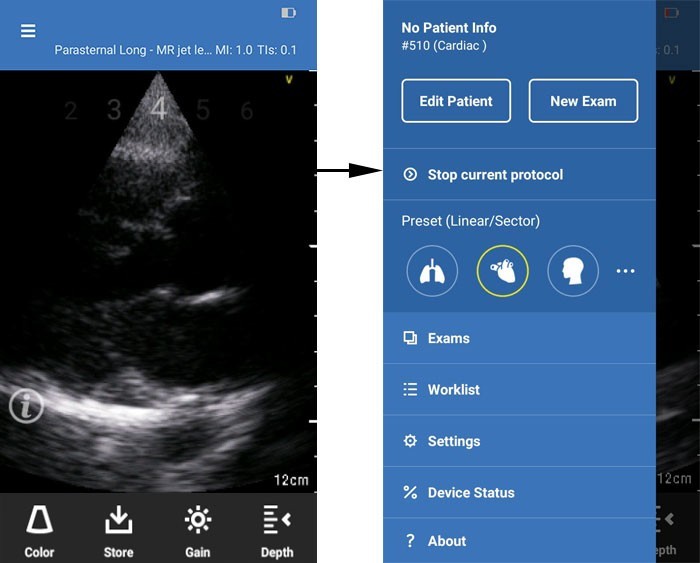

NOTE: If you wish to stop the protocol anytime in the middle of a scan, press the Menu icon on the header. Press “Stop current protocol” to exit.

Stop protocol